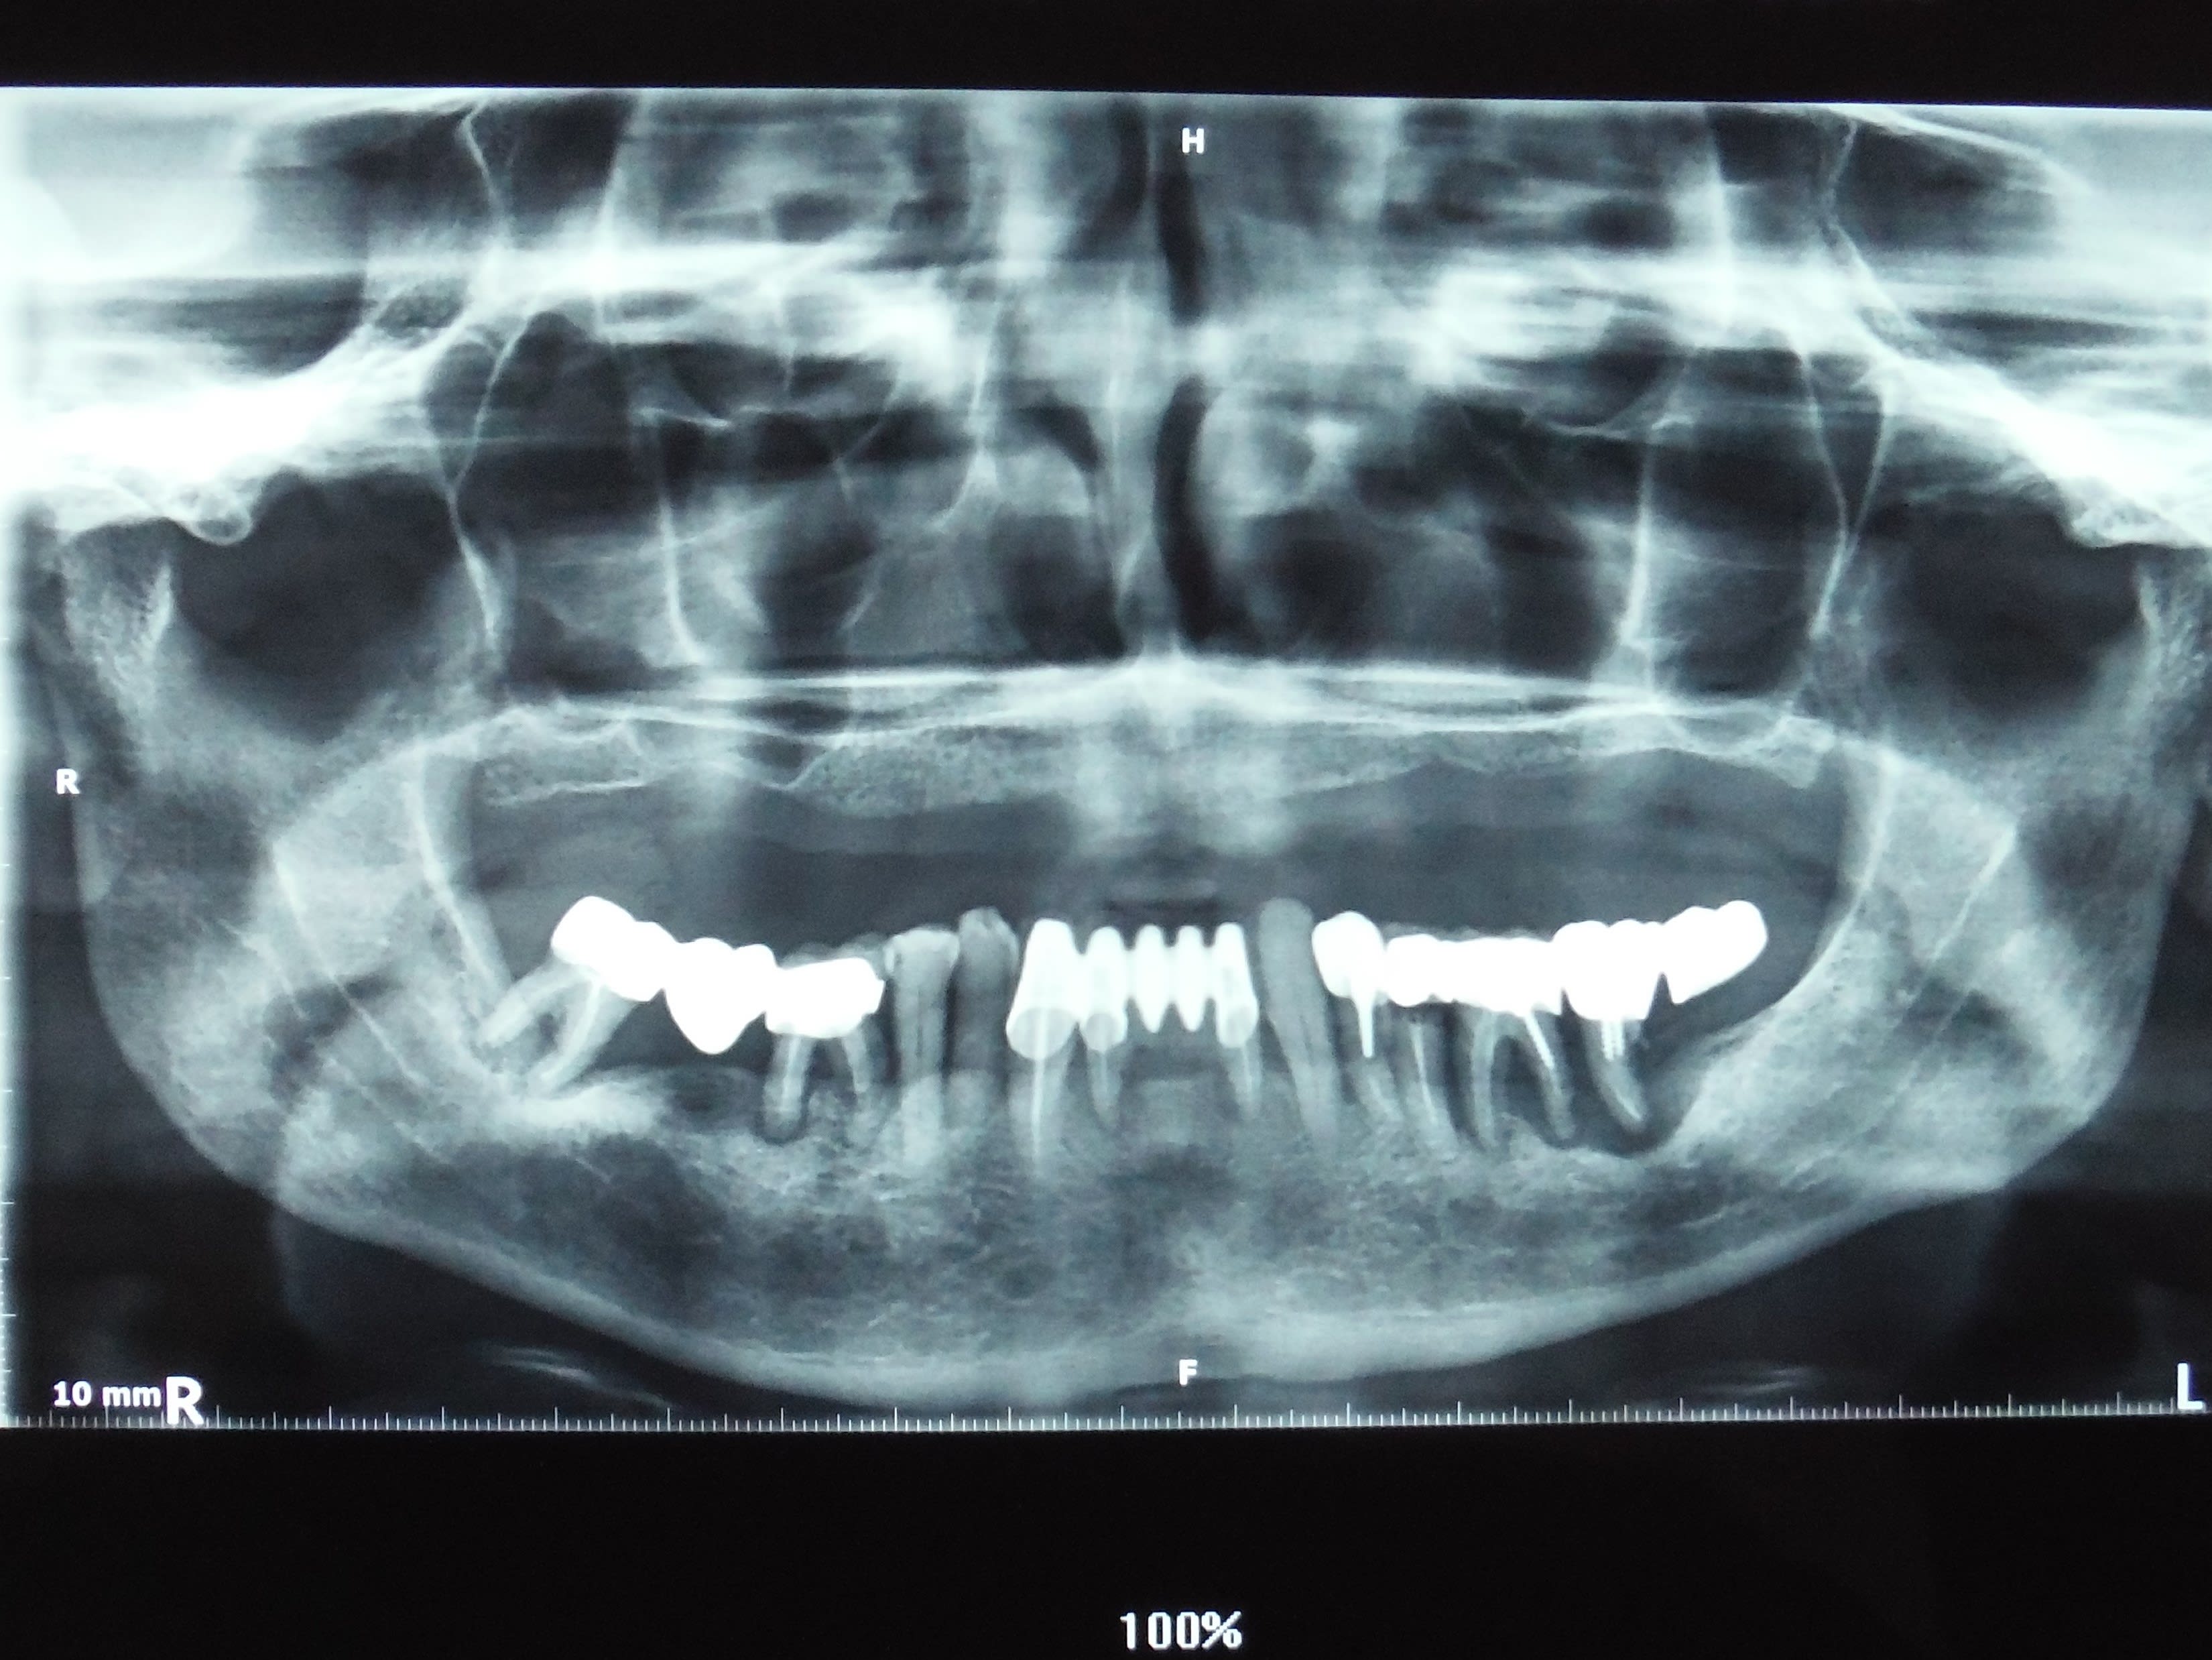

Cas « langue de bovin » terminé

769ebde5 a38e 4211 ba00 1d32b8ee5260 ltw6gn - Eugenol

vulpi

Nan Junior, pour une fois c'est pas une connerie ce que je vais te dire, cas terminé dans 7 à 10 ans si RAS. Avant prudence.

j’espère que dans 10 ans ça sera toujours en place car étant donné le nombre d’implants que j’ai posés ça me ferait bien chier de réintervenir :))

il est propre ton cas fini de la charolaise .

les courbes sont belles , le recouvrement aussi ....